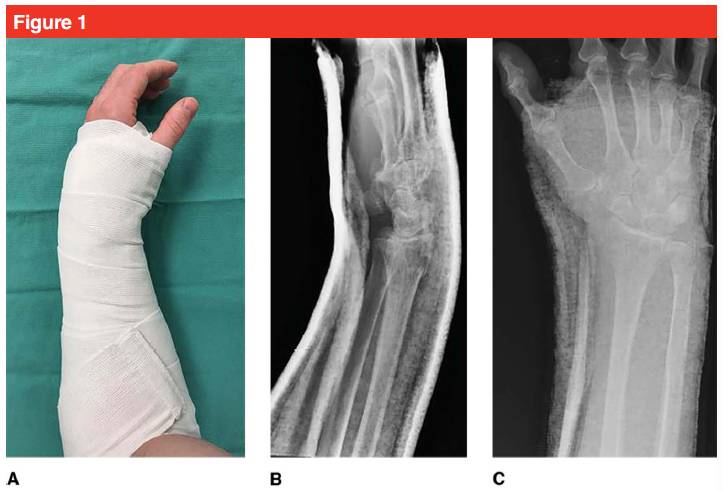

В нашем центре переломы дистального отдела лучевой кости с минимальным смещением обычно иммобилизуют гипсовой лонгетой Sugar Tong над локтем, чтобы ограничить пронацию и супинацию локтя (см. рис. 1).Если смещение перелома велико, после закрытой репозиции следует наложить шину сахарного щипца.Обратите внимание, что при выполнении иммобилизации гипсовой лонгетой область иммобилизации должна останавливаться на проксимальном конце пальца, чтобы облегчить движение пальца и предотвратить скованность.Использование эластичных бинтов для ограниченной компрессионной фиксации может помочь при шинировании.Тип перелома определяет метод закрытой репозиции.При необходимости может быть выбрана местная гематомная анестезия дистального отдела лучевой кости, а затем выполняется тракционная редукция путем оттягивания пальцев (указательного и среднего) для коррекции деформации и восстановления лучезапястного сочленения.Тракционное вправление обычно проводят по обратному механизму перелома.Тракционная редукция в разных плоскостях необходима для завершения восстановления связок и восстановления соосности отломков перелома, головки и полулунной кости.На коронарной плоскости восстановите анатомическое выравнивание локтевой и лучевой костей, дистального фрагмента кости и диафиза лучевой кости.Репозиция типичного перелома Коллеса требует, чтобы ассистент удерживал большой палец пациента в одной руке и 4 пальца пациента в другой руке, применяя контртракцию для отделения фрагмента перелома от метафиза лучевой кости, продолжая продольную тракцию, а затем ладонную.Сгибание и отклонение локтевой кости помогают вправить фрагмент перелома.У пациентов пожилого возраста с повреждением окружающих мягких тканей в процессе вправления требуются осторожные манипуляции во избежание разрывов кожи (во время вправления можно использовать ватный диск).После репозиции проводят сосудисто-нервное исследование.

Рисунок 1. (A) Пациент с переломом дистального отдела лучевой кости был иммобилизован в слегка нейтральном положении ладони с помощью гипсовой шины Sugar Tong для предотвращения повторного смещения;(B) и (C) переднезадняя и боковая рентгенограммы, показывающие хорошую фиксацию запястья пациента.Гипсовая лонгета не выходит за пределы головки пястной кости, чтобы пальцы могли нормально двигаться.